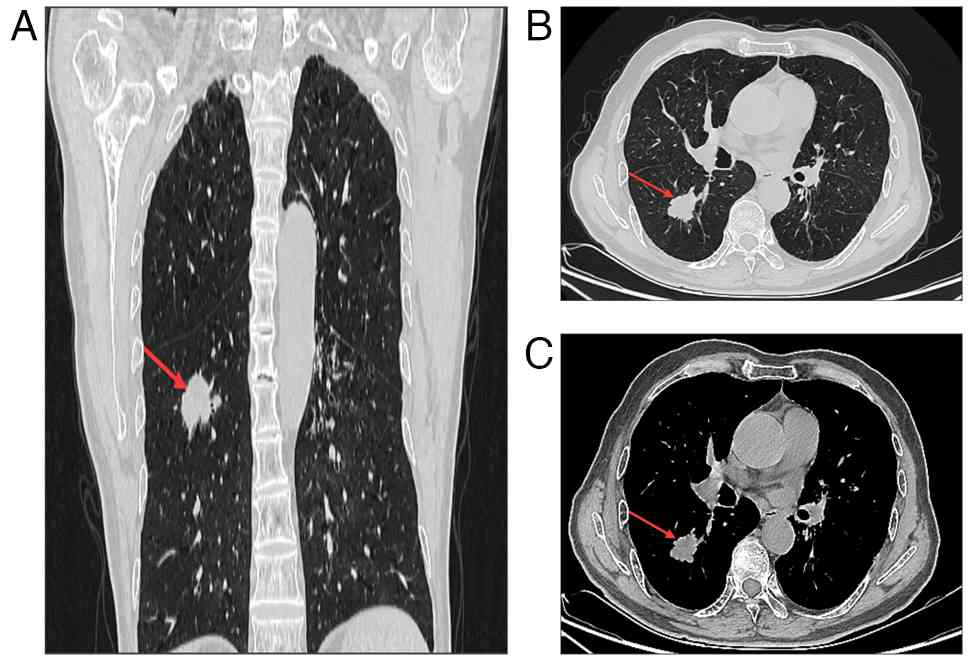

A 69-year-old man first presented to The Second Hospital of Lanzhou University (Lanzhou, China) in June 2021 with a chronic cough but without dyspnea for 2 months, and with no history of pulmonary disease. The patient had smoked 15 cigarettes daily for 43 years and had not experienced recent weight loss. Throughout the 2-month period, the patient had maintained a good mental status and a clear consciousness, with appetite being unaffected and sleep being undisturbed. Normal bowel movements were noted, with no symptoms of urinary frequency, urgency, pain or hematuria. A physical examination indicated normal skin and conjunctiva, clear lung breath sounds, no tenderness or rebound tenderness in the abdomen, painless percussion over the kidney area and no lower limb swelling. The patient had been diagnosed with depression 3 years previously and had no other surgical or traumatic history. Computed tomography (CT) revealed a mass in the dorsal segment of the lower lobe of the right lung, measuring ~3.3×2.6×2.5 cm, along with enlargement of the mediastinal and hilar lymph nodes (Fig. 1). Additional imaging, including contrast-enhanced abdominal CT, magnetic resonance imaging (MRI) of the brain and a bone scan, revealed no abnormalities. Based on these findings, the patient was clinically staged as stage IB (cT2aN0M0), according to the TNM classification system (19).

Computed tomography scan of the chest.

(A) A lobular soft-tissue mass measuring ~33×26×25 mm was visible

in the right lung. In addition, the mass was visible in both (B)

lung window and (C) mediastinal window views. Lesions are indicated

by red arrows.

Figure 1.

Computed tomography scan of the chest. (A) A lobular soft-tissue mass measuring ~33×26×25 mm was visible in the right lung. In addition, the mass was visible in both (B) lung window and (C) mediastinal window views. Lesions are indicated by red arrows.